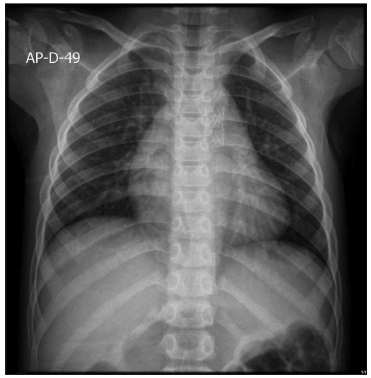

Considere a imagem a seguir.

Diante do exposto, assinale a alternativa que apresenta corretamente qual é o tratamento realizado por esse paciente.

Comissurotomia pulmonar.

Aortoplastia e colocação de

stent

.

Arterioplastia de pulmonar direita por cateter-balão e colocação de

Bandagem de artérias pulmonares.

Colocação de prótese implantável em posição tricúspide (

valve in valve

).